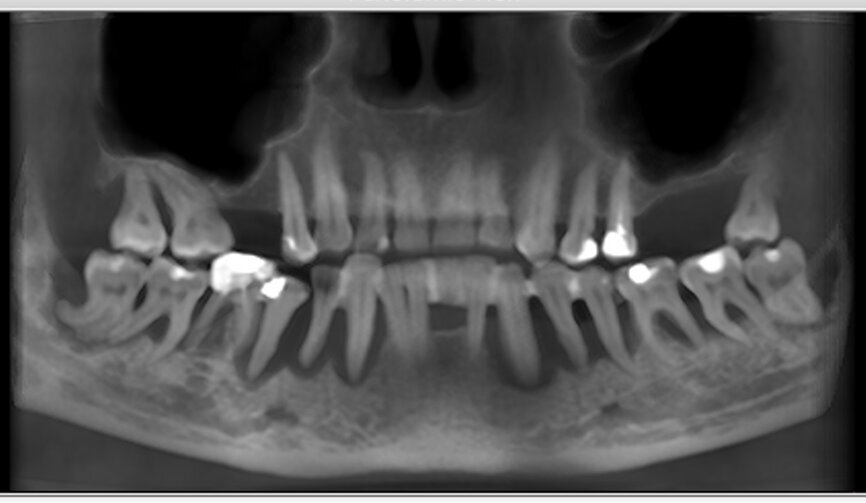

Wykonanie badania tomograficznego potwierdziło diagnozę o zaawansowanej nierokującej chorobie przyzębia (Ryc. 2). Po konsultacji została podjęta decyzja o ekstrakcji wszystkich zębów w żuchwie, natychmiastowym wprowadzeniu implantów z jednoczesną czasową odbudową protetyczna stałą mocowaną na wszczepionych implantach. Zlecono rutynowe badanie lekarskie i laboratoryjne.